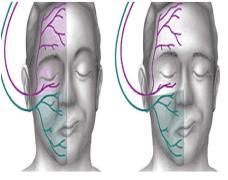

Fase 3 FARINGEA. Esta fase es involuntaria. Se inicia cuando los mecanorreceptores de la faringe envían señales a nuestro cerebro y este activa el reflejo deglutorio, que se caracteriza por una secuencia de movimientos que cierran la nasofaringe y la vía respiratoria elevando el cartílago hioides, bajando el cartílago epiglotis y cerrando la glotis donde están las cuerdas vocales y más abajo el acceso a los pulmones por la tráquea. De este modo solo queda abierta la vía esofágica por la que se desliza el bolo con la ayuda de los musculos constrictores de la faringe.

– Pérdida de alimento por una de las comisuras. Esto se debe a una alteración de la sensibilidad, de la fuerza y movilidad de un lado de la cara por una hemiparesia facial del lado contrario al hemisferio cerebral afectado por el ictus.